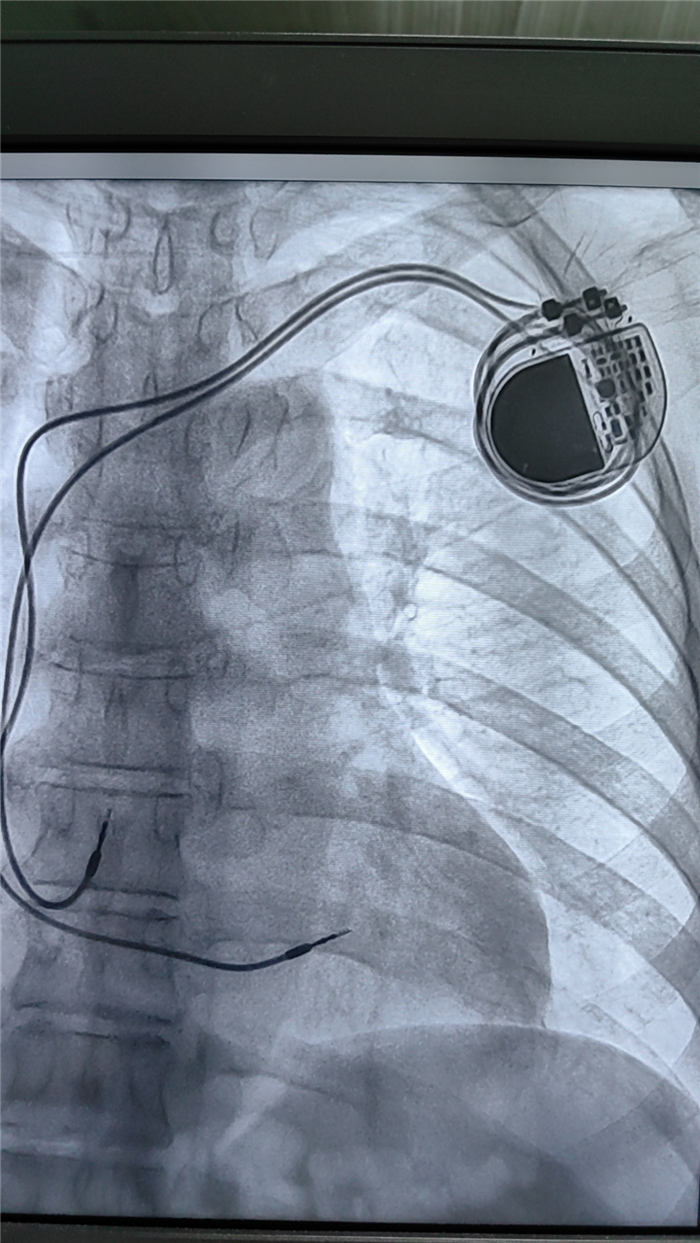

640 (1)

起搏器植入成功